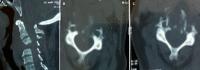

Tuberculosis is a major public health problem in the world. Spinal tuberculosis (Pott disease) is a frequently encountered extrapulmonary form of the disease. Cervical spinal tuberculosis is relatively rare. We report the case of a 66-year-old patient admitted for cervical Pott's disease managed surgically and the positive outcome. A patient with a history of pulmonary tuberculosis present 3 months ago persistent neck pain with tingling and heaviness in both upper limbs. The neurological examination was normal without any sensory or motor deficit. Spinal cord magnetic resonance imaging (MRI) showed a lesion centered on the vertebral body of C4 with spinal cord compression and epiduritis without signs of spinal cord injury. The patient underwent a corpectomy of C3 and C4 with an iliac graft and anterior cervical plate. The anatomopathological examination revealed a Pott disease. He was therefore put on antituberculous chemotherapy for 12 months. Three months later the neck pain and tingling disappeared in the upper limbs. Cervical Pott's disease is relatively rare. Surgical management is indicated in the case of spinal instability or spinal cord compression.